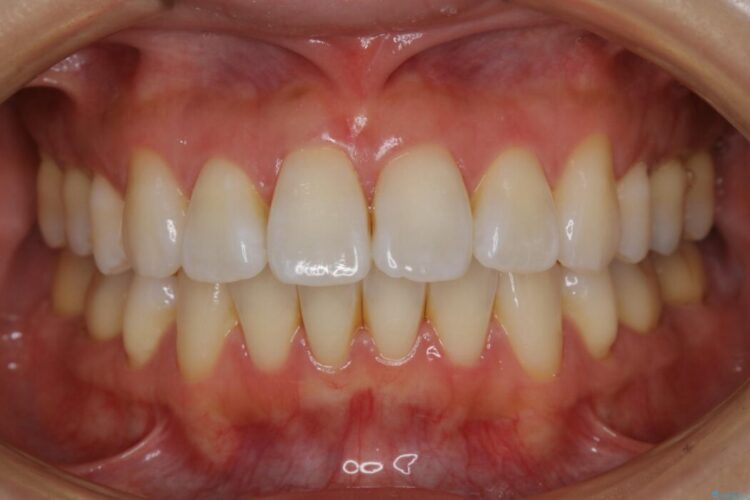

【20代女性】矯正後の後戻り、出っ歯の改善

抜歯矯正後の上の前歯の後戻りが気になるとご来院された患者様です。

歯と歯の間を削るのと、歯列のU字型のアーチを僅かに外側に広げる事でスペースを作り、前歯の角度の改善をしました。